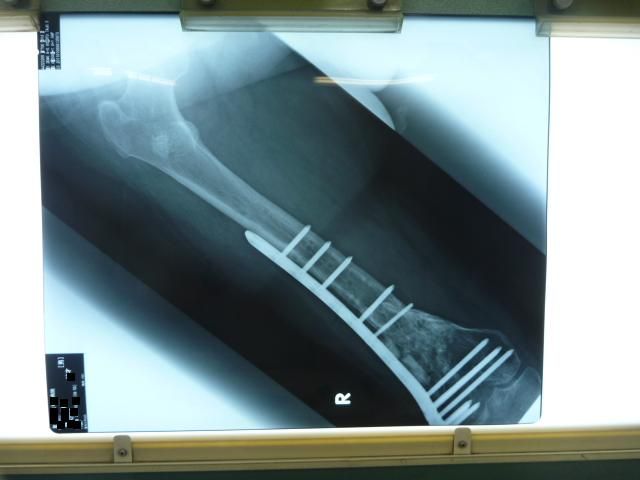

µ×¡¹¤Î¥ì¥ó¥È¥²¥ó

º£Ç¯¤Î¼ê½Ñ¤ÎͽÄê¤ò·è¤á¤ë¥ì¥ó¥È¥²¥ó¤ò»£±Æ¤·¤Þ¤·¤¿¡£

ΩÇɤʤªÊõ¤¬¼Ì¤Ã¤Æ¤Þ¤¹¤¬¡¦¡¦¡¦

¿Ç»¡·ë²Ì¤Ï¡¦¡¦¡¦

¡Ö¹ü¤Ï¿ïʬ¤·¤Ã¤«¤ê¤·¤Æ¤¤Æ¤¤¤ë¤±¤É

¤â¤¦¾¯¤·ÍͻҤò¸«¤è¤¦¤«¡¦¡¦¡¦¡×

¤È¸À¤¦»ö¤Ë¤Ê¤ê¤Þ¤·¤¿¡£

´°Á´¤Ë¹ü¤¬½ÐÍè¾å¤¬¤Ã¤Æ¤Þ¤¹¡£

¤³¤Î¥×¥ì¡¼¥È¤ò¼è¤ë»þ¤Ë

¤â¤¦¾¯¤·¶Ê¤²¤ì¤ëÍͤˤʤë¤Ï¤º¤Ç¤¹¡£

ΩÇɤʤªÊõ¤¬¼Ì¤Ã¤Æ¤Þ¤¹¤¬¡¦¡¦¡¦¿Ç»¡·ë²Ì¤Ï¡¦¡¦¡¦

´°Á´¤Ë¹ü¤¬½ÐÍè¾å¤¬¤Ã¤Æ¤Þ¤¹¡£¤³¤Î¥×¥ì¡¼¥È¤ò¼è¤ë»þ¤Ë